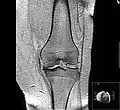

MRI of osteoarthritis in the knee, with characteristic narrowing of the joint space

Primary osteoarthritis of the left knee. Note the osteophytes, narrowing of the joint space (arrow), and increased subchondral bone density (arrow).